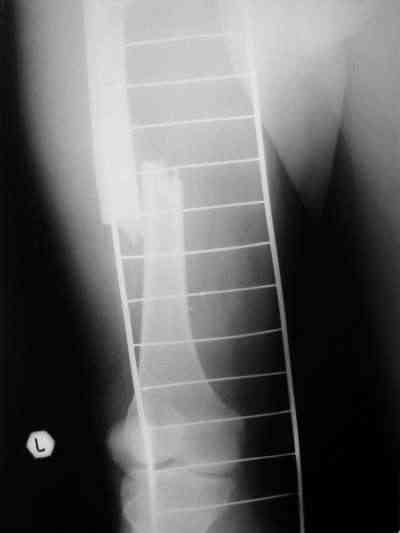

Около 10 дней назад выполнил остеосинтез бедренной кости LC-DCP и DHS по поводу фрагментарного оскольчатого перелома в средней трети и чрезвертельного перелома.

Снимки в приложении.

В приложении и имеющийся в наличии брейс. Приношу извинения за низкое качество снимков.

Качество снимков приемлемое. С нагрузкой категорически не надо спешить - только при уверенных рентгенологических признаках сращения на обоих уровнях в данном случае. Т.е. не только на диафизе, но и в вертельной области. При безупречном синтезе DHS ранняя нагрузка в этой зоне была бы безопасна, все определялось бы сращением диафиза. А поскольку винт в DHS сделали ну о-очень короткий, то ойкнуть не успеете, как

проксимальный отдел бедра в варус кувыркнется.

Уважаемый Никита, очень меня расстроило не качество снимков, а сам остеосинтез. Вертельный перелом, пожалуй, еще срастется. А диафиз может преподнести ожидаемое, предуготованное осложнение: несращение и перелом импланта, даже если это суперфмрменная пластина.:(